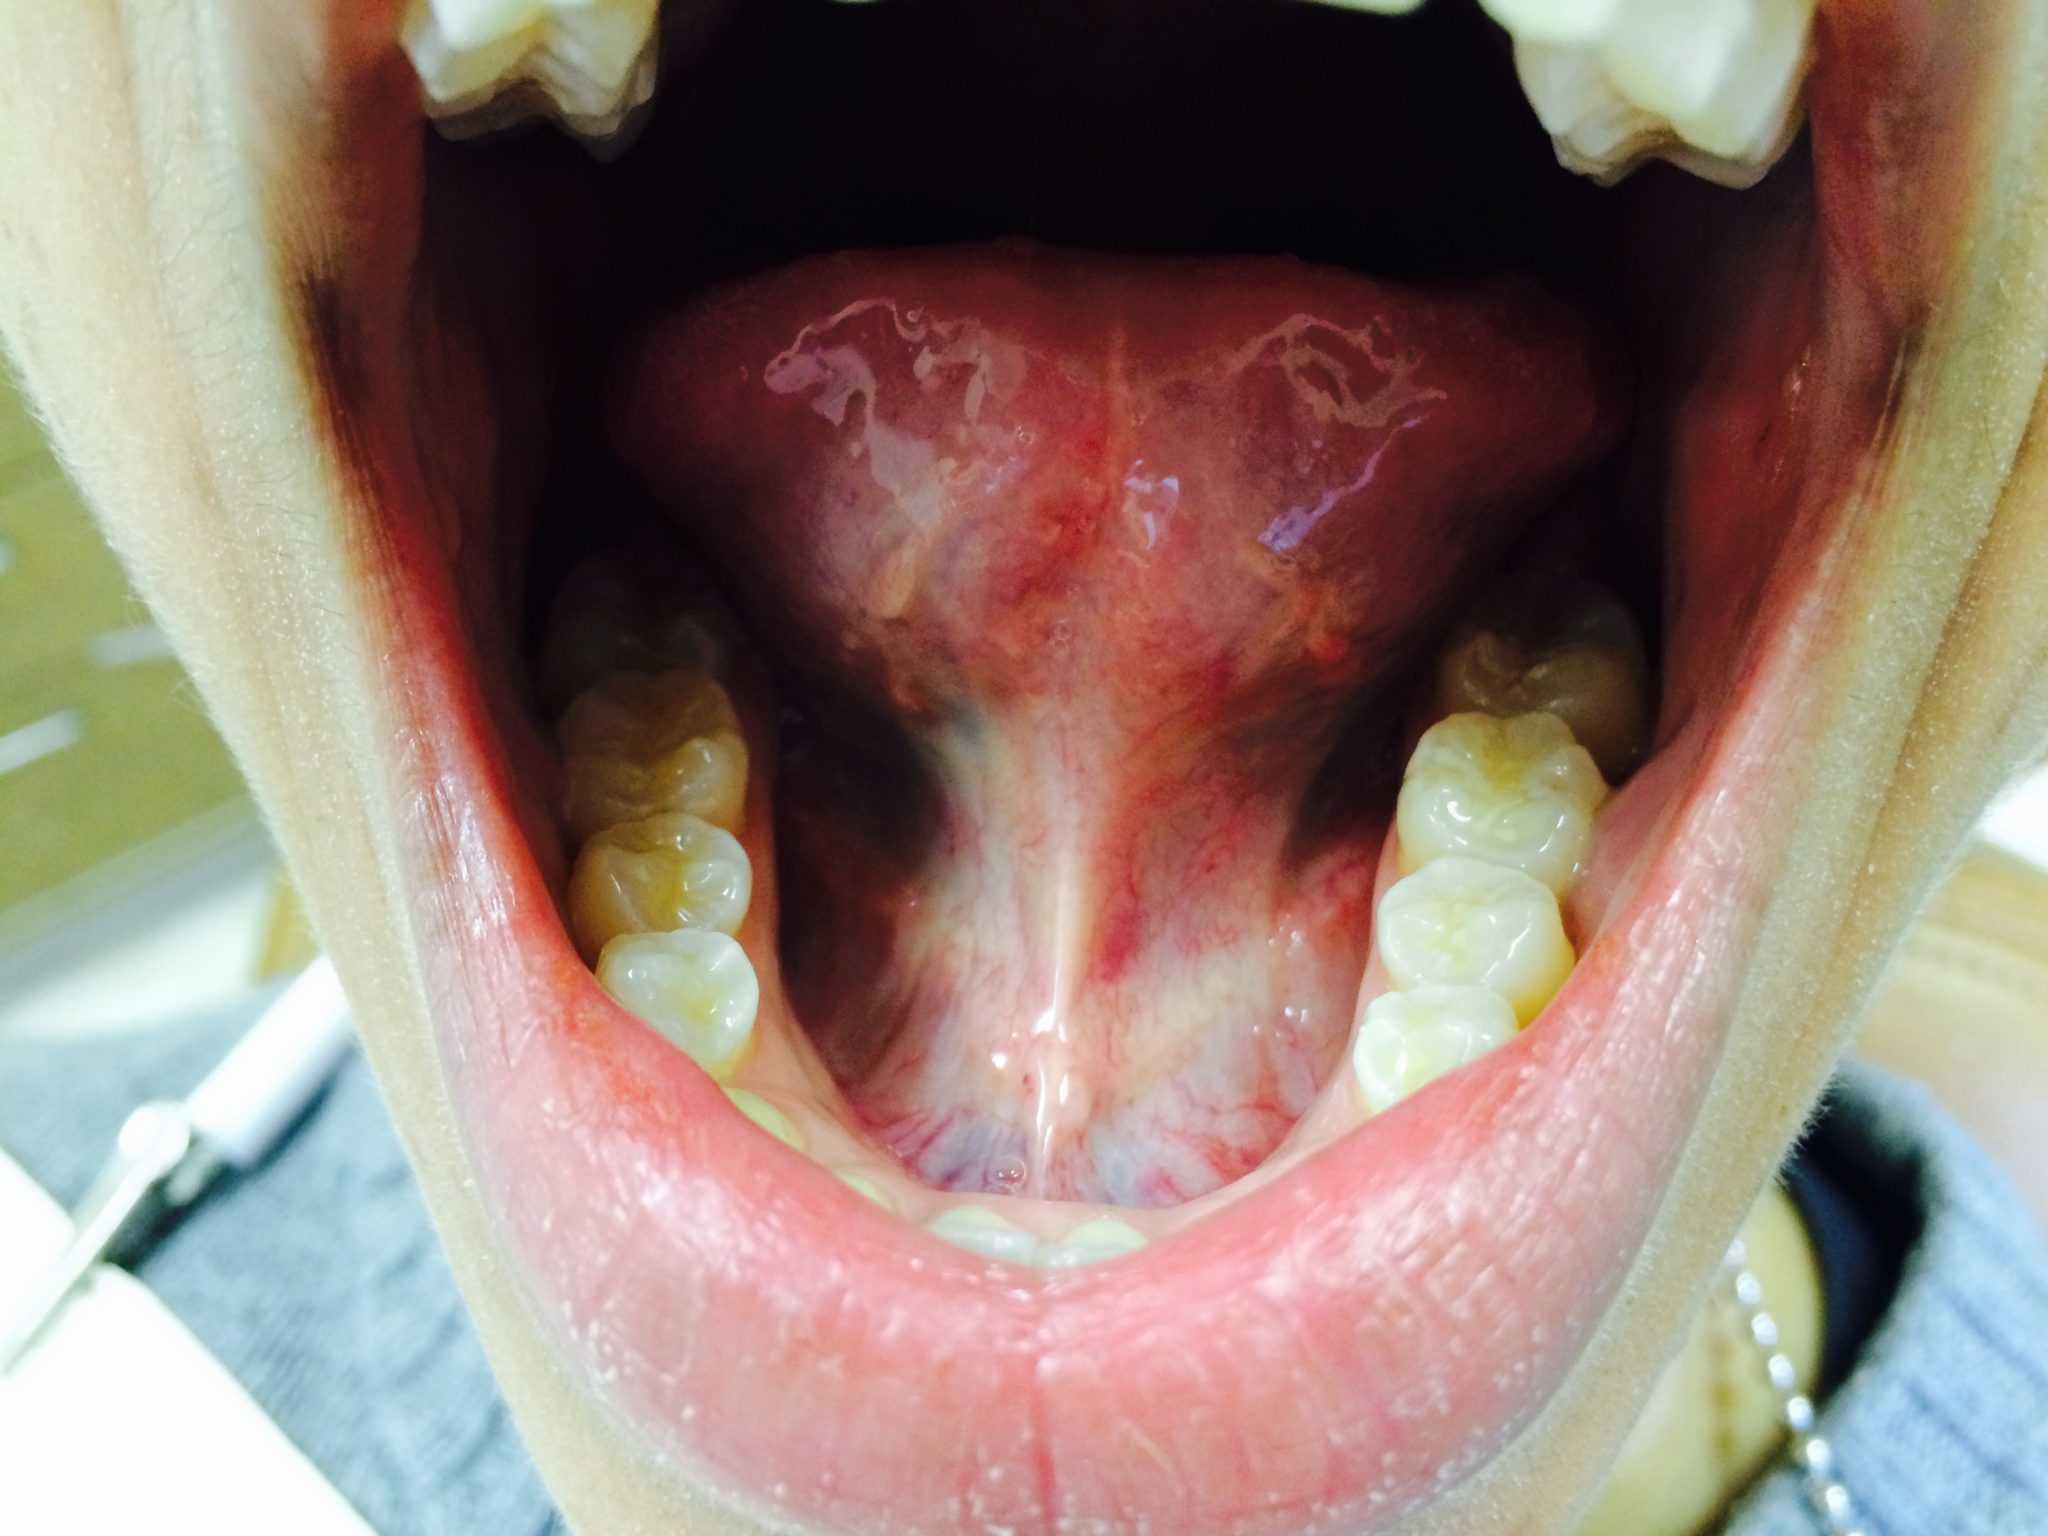

Tongue Tie Reattachment Pictures A Visual Guide to the Procedure

Tongue Tie Reattachment Pictures A Visual Guide to the Procedure How Long Does It Take Tongue Tie Surgery To Heal It can affect feeding, speech. The normal healing process may result in a white diamond shape under your baby’s tongue. Find out the four phases of healing and the benefits of. You should give your baby frequent feeds for the next few days. When your child is asleep, the surgeon cuts the skin of the. This heals by itself and. How Long Does It Take Tongue Tie Surgery To Heal.